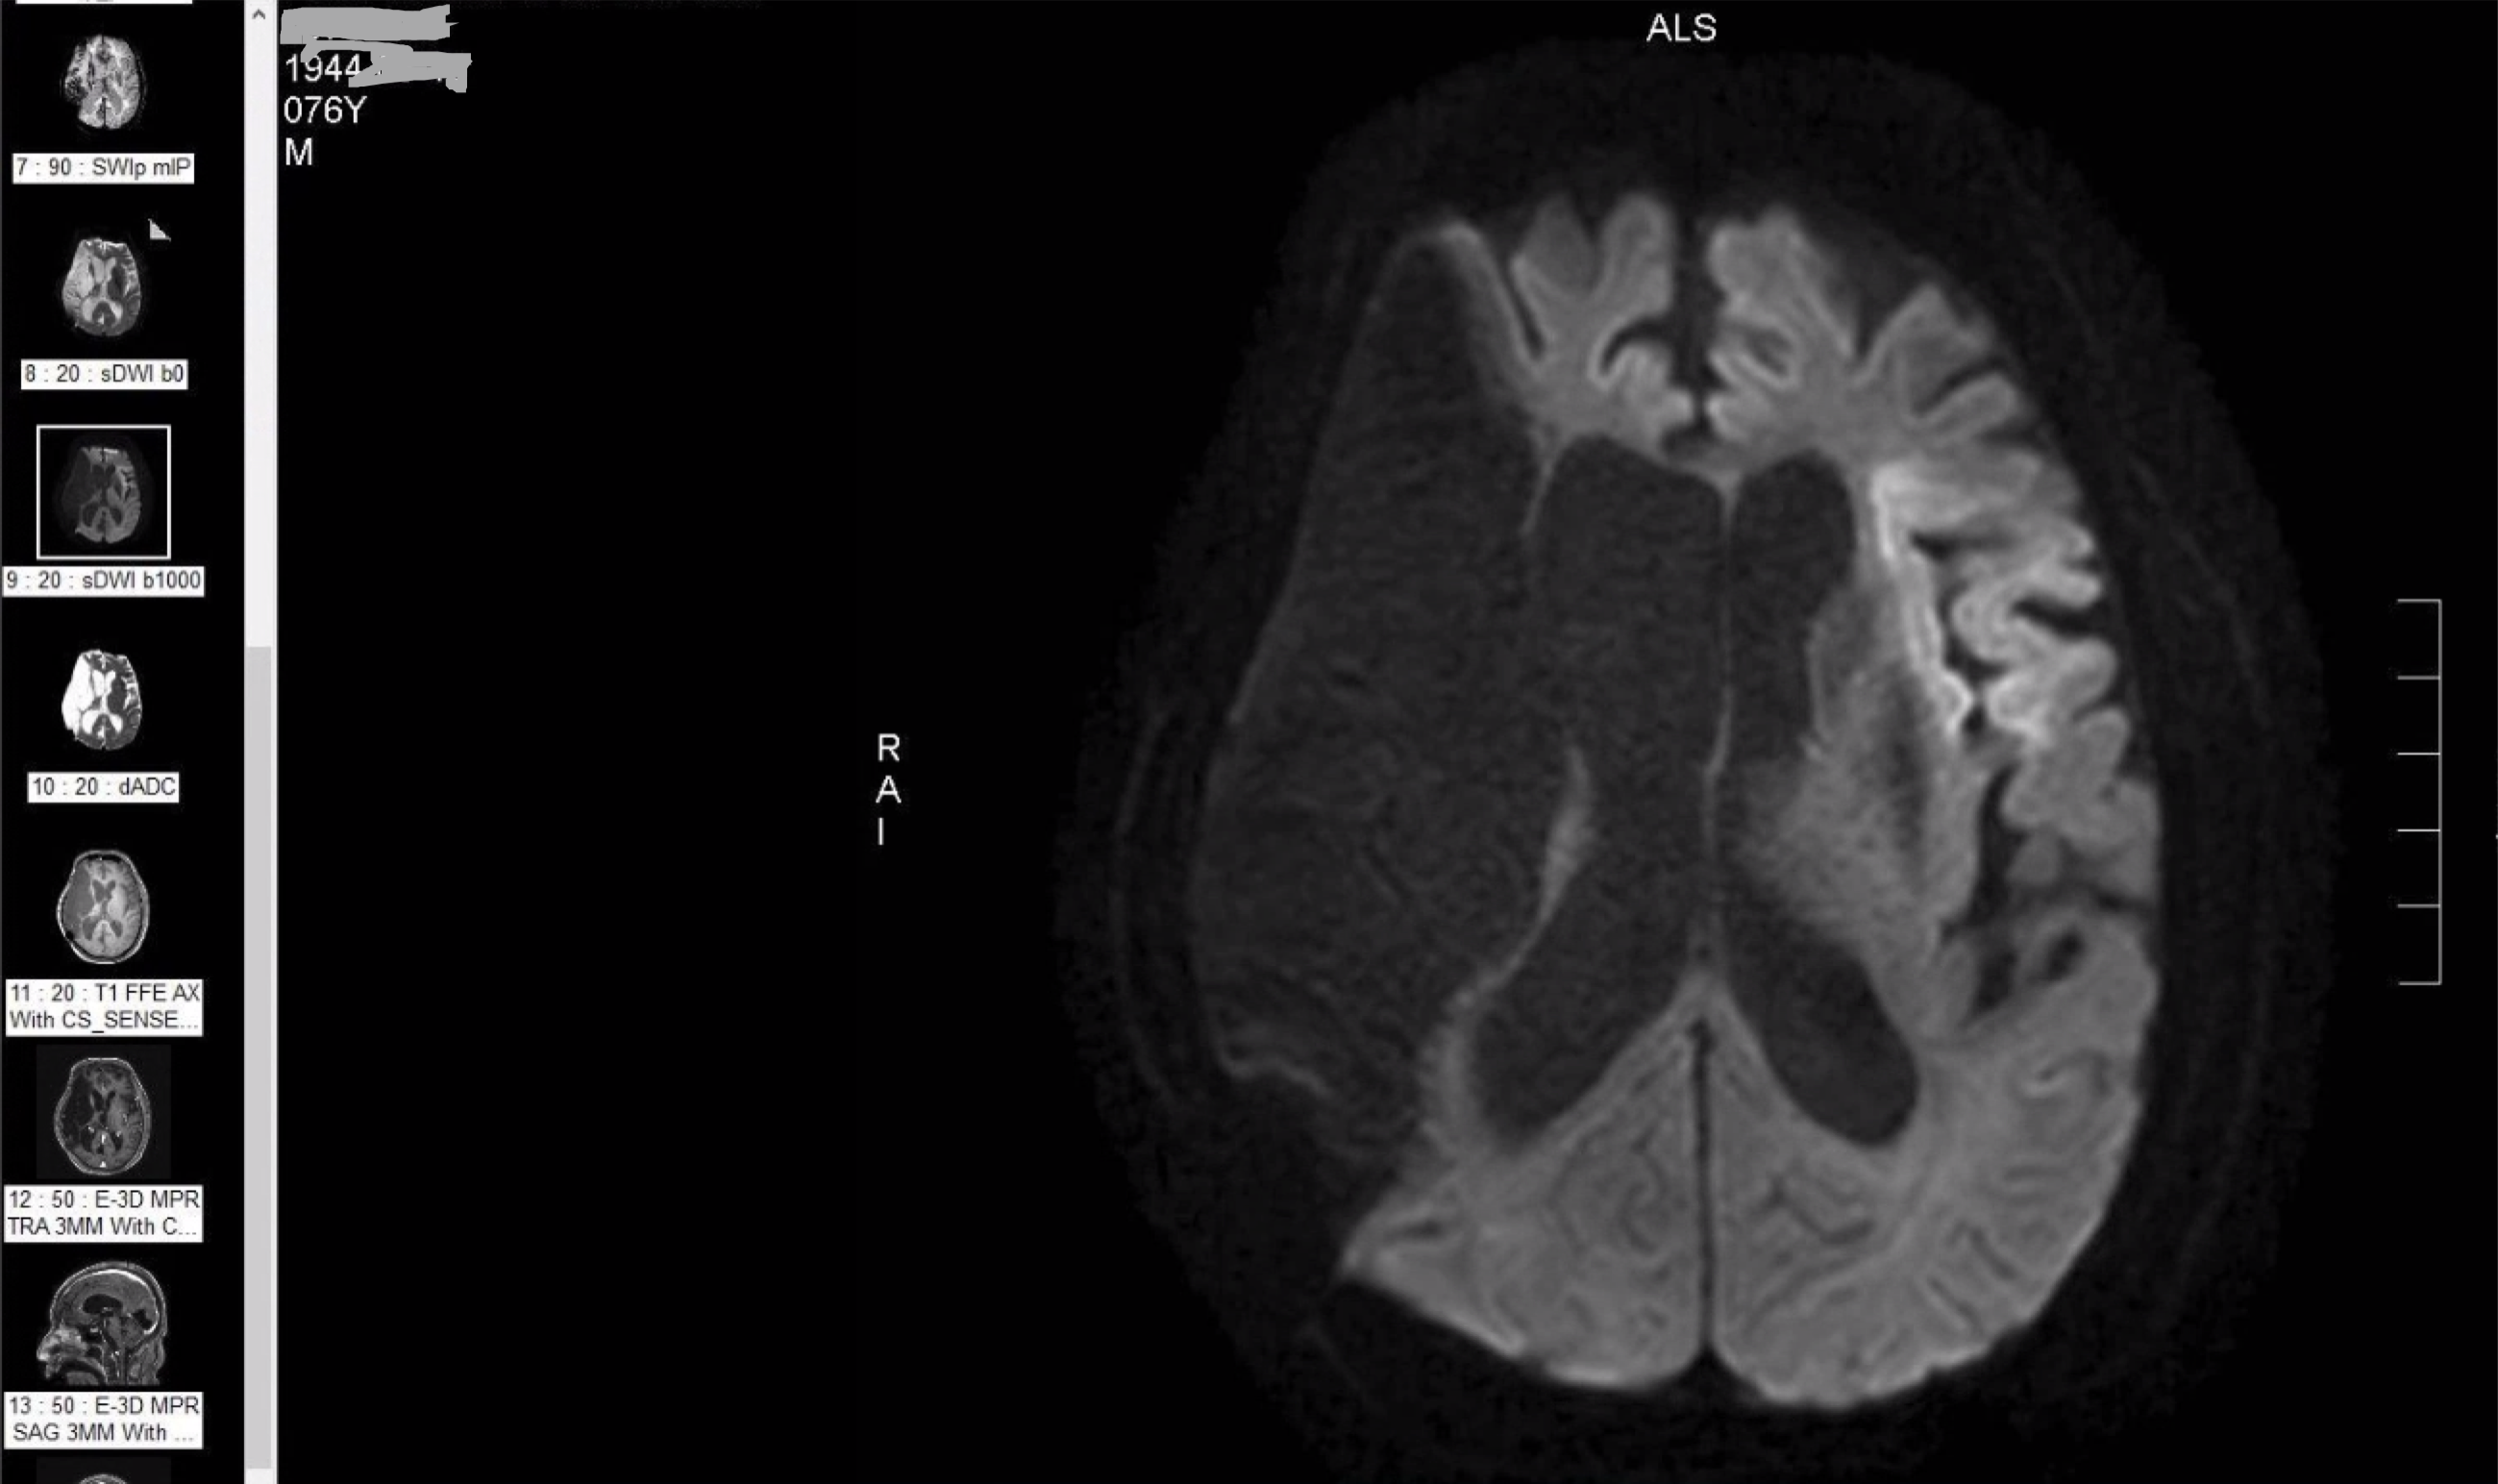

M/76

right hemiplegia due to left cerebral infarction 2020.9.12.

- left insula, frontal area

aphasia